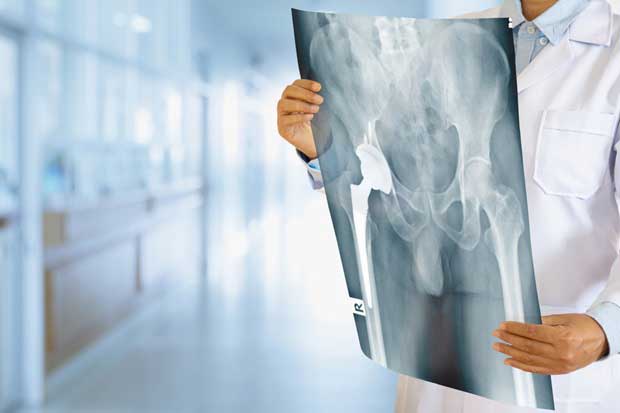

Total Hip Replacement (THR): In a total hip replacement, both the ball (the head of the femur) and the socket (acetabulum) of the hip joint are replaced with prosthetic components. This is the most common type of hip replacement.

Partial Hip Replacement (Hemiarthroplasty): In a partial hip replacement, only the ball portion of the hip joint (the femoral head) is replaced with a prosthetic component. This is typically done when the socket part of the hip joint is still healthy and doesn't need replacement. Hemiarthroplasty is often performed for certain hip fractures.

Revision Hip Replacement: In cases where a previous hip replacement has failed or become damaged, a revision hip replacement may be necessary. This involves removing and replacing the existing prosthetic components with new ones.

Hip Implants Material: The prosthetic components of hip replacements can be made from various materials, including metal, plastic, and ceramic. The choice of material depends on factors like patient age, activity level, and the surgeon's recommendations.